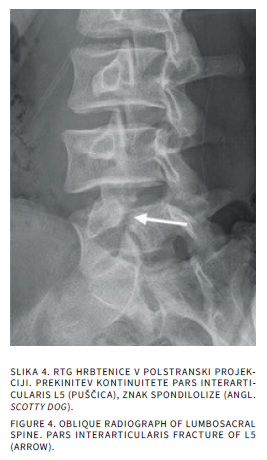

Bolečine v mišičnoskeletnem sistemu so v otroškem obdobju sorazmerno pogoste. Delimo jih na akutne in kronične, slednje trajajo več kot 3 mesece. Diferencialna diagnoza tako akutnih kot kroničnih bolečin v sklepih pri otrocih je široka. Slikovne preiskave so poleg anamneze, klinične slike in laboratorijskih izvidov pomembne v diagnostičnem postopku iskanja vzrokov bolečine. Katero slikovno metodo uporabimo najprej, je odvisno od mesta bolečine in od prizadetosti tkiva. Pri mehkotkivnih spremembah in oteklinah sklepov je prva diagnostična metoda ultrazvočna preiskava, pri sumu na prizadetost kosti pa rentgensko slikanje. Če je potrebno, sledi magnetnoresonančno slikanje ali računalniška tomografija. V prispevku bomo opisali anatomske in morfološke značilnosti otroškega skeleta, ki lahko dajejo videz patoloških sprememb ter slikovne diagnostične postopke pri akutnih in kroničnih bolečinah v sklepih.